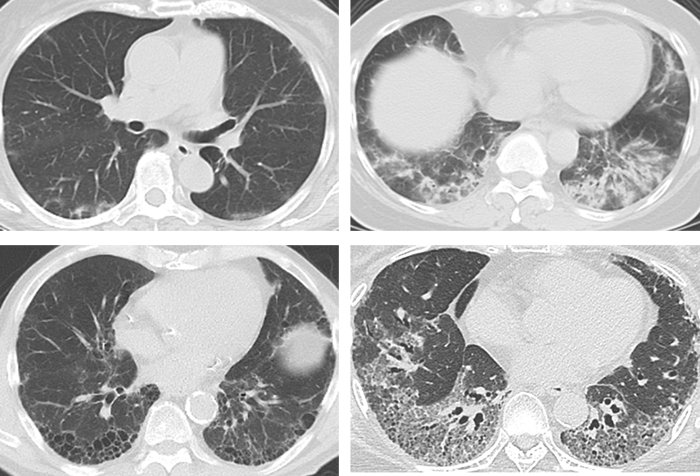

主な症状として、痰を伴わない咳が出る、動くと息が切れやすい、息を深く吸えないといった肺に関連した症状が出現します。しかし、病気が発症してまもない時期や肺の炎症が軽微な場合には、これらの症状は乏しく、肺の病状がある程度進行してから、症状が出現することもあります。また、以下の肺画像(図3)に示すように、個々の患者さんで、肺炎の分布や進行スピードなど特徴パターンが異なるため、症状の出現の仕方が異なります。

図3. 間質性肺疾患のコンピューター断層撮影(CT)画像(個々の患者さんによって肺炎の分布や画像特徴は異なります)